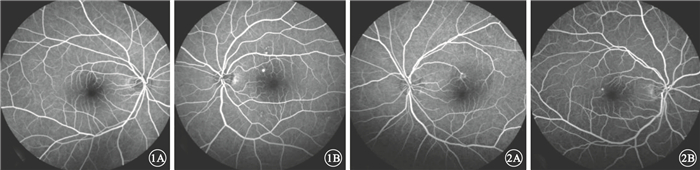

患者中,男性57例,占74.0%;女性20例,占26.0%。年齡26~63歲,平均年齡46歲。病程3 d~1年,平均病程13周。單眼發病73例,占94.8%;雙眼發病4例,占5.2%。單眼發病的73例患者中,右眼發病45例,占所有患者的58.4%;左眼發病28例,占所有患者的36.4%。急性CSC (圖 1)47只眼,占患眼的58.0%;慢性CSC(圖 2) 34只眼,42.0%。患眼視力0.12~1.0。

圖1

急性CSC患眼FFA像。1A.右眼,拱環鼻上方滲漏點,周圍呈弱熒光;1B.左眼,拱環鼻上方滲漏點,周圍呈弱熒光??圖 2?慢性CSC患眼FFA像。2A.左眼,拱環上方點狀強熒光滲漏點,周圍呈弱熒光;2B.右眼,拱環顳側點狀強熒光滲漏點,周圍呈弱熒光

圖1

急性CSC患眼FFA像。1A.右眼,拱環鼻上方滲漏點,周圍呈弱熒光;1B.左眼,拱環鼻上方滲漏點,周圍呈弱熒光??圖 2?慢性CSC患眼FFA像。2A.左眼,拱環上方點狀強熒光滲漏點,周圍呈弱熒光;2B.右眼,拱環顳側點狀強熒光滲漏點,周圍呈弱熒光

患者中,男性57例,占74.0%;女性20例,占26.0%。年齡26~63歲,平均年齡46歲。病程3 d~1年,平均病程13周。單眼發病73例,占94.8%;雙眼發病4例,占5.2%。單眼發病的73例患者中,右眼發病45例,占所有患者的58.4%;左眼發病28例,占所有患者的36.4%。急性CSC (圖 1)47只眼,占患眼的58.0%;慢性CSC(圖 2) 34只眼,42.0%。患眼視力0.12~1.0。

圖1

急性CSC患眼FFA像。1A.右眼,拱環鼻上方滲漏點,周圍呈弱熒光;1B.左眼,拱環鼻上方滲漏點,周圍呈弱熒光??圖 2?慢性CSC患眼FFA像。2A.左眼,拱環上方點狀強熒光滲漏點,周圍呈弱熒光;2B.右眼,拱環顳側點狀強熒光滲漏點,周圍呈弱熒光

圖1

急性CSC患眼FFA像。1A.右眼,拱環鼻上方滲漏點,周圍呈弱熒光;1B.左眼,拱環鼻上方滲漏點,周圍呈弱熒光??圖 2?慢性CSC患眼FFA像。2A.左眼,拱環上方點狀強熒光滲漏點,周圍呈弱熒光;2B.右眼,拱環顳側點狀強熒光滲漏點,周圍呈弱熒光